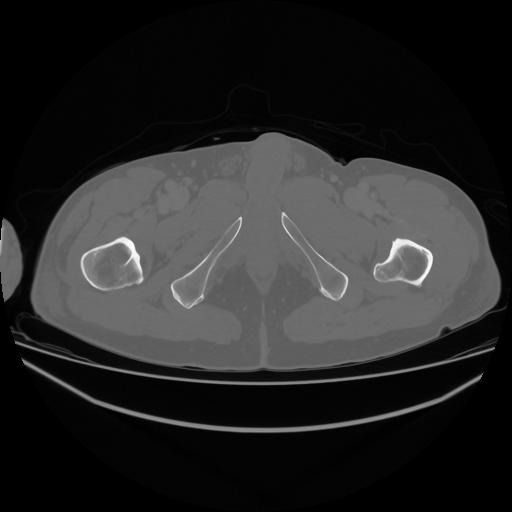

5 CUERPO,CE,Vol,1.0,CUERPO,,